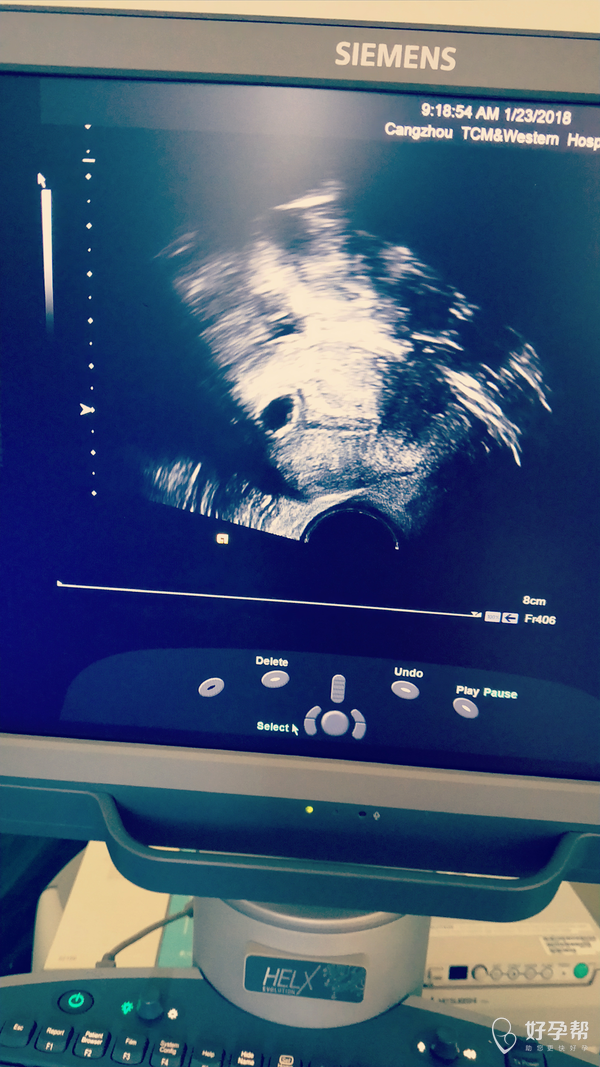

医生帮我看看有胎芽吗

你好啊,这个胎芽不是太明显,这个只能观察看看。

冻囊胚第33天做的复查,帮我看看有胎芽吗?从0.6乘0.5吃了八天的药复查才长到0.9乘0.8,一直在就褐色,今天就流血了